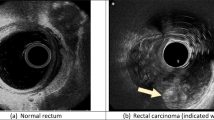

The study aimed to explore the performance of deep learning-based hysteroscopy intelligent examination combined with ultrasound examination in the diagnosis of endometrial carcinoma (EC). Specifically, 80 EC patients, diagnosed by hysteroscopic cervical tissue biopsy were selected as the research subjects, and they were divided into the experimental group, and the control group. The Dense-Pyramid-Attention U-Net (DPA-UNet) algorithm image processing method based on deep learning was applied to diagnose patients in the experimental group. Then, different diagnosis methods were compared for the accuracy rates of the preoperative staging and the diagnosis results. The results showed that compared with U-Net and Dense-Net models, the image clarity processed by the DPA-UNet model was improved and the lesion site was clearer, and its Dice similarity coefficient (DSC), precision, and recall were 80.4 ± 18%, 80.1 ± 15%, 87.6 ± 11%, respectively, higher than those of U-Net and Dense-Net model, and the difference wax statistically significant (P < 0.05); the diagnosis result coincidence rate of the experimental group was 91.8%, significantly better than that of the control group 64.1%, and the difference was statistically significant. In conclusion, the deep learning-based hysteroscope intelligent inspection system combined with ultrasound images may provide an efficient way for early diagnosis of EC.